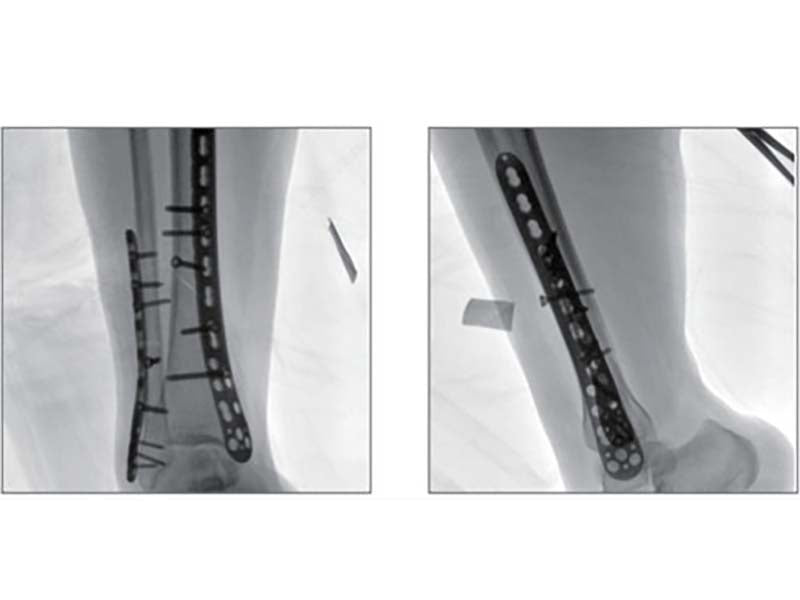

Compared to the conventional 9” image intensifier, a 9” x 9” flat panel detector is able to expand the FoV by 22%, providing more perspective for clinical diagnosis.

Eliminating distorted image caused by electron beam deflection, presenting actual vision of anatomical structure.